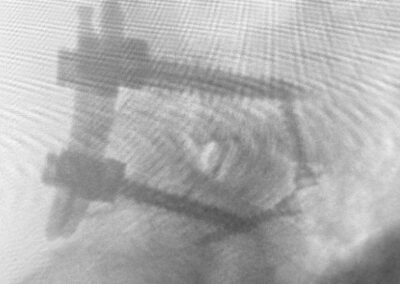

Figuras demonstrando os parafusos posteriores, o cage PLIF consolidado